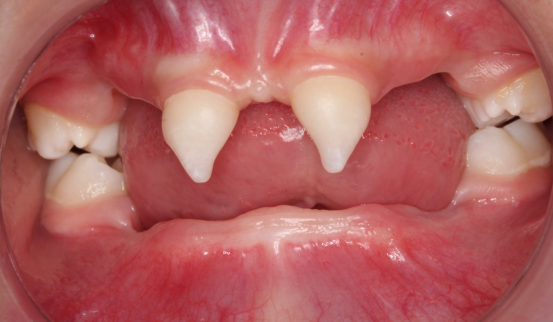

近年来,williamhill官网附属口腔医院(后文简称贵医口腔)在临床诊疗方面每年均有多个技术创新或突破。期间,副经理、口腔修复种植科主任医师王永曾带领团队完成多名外胚层发育不全患儿的可摘局部义齿及全口义齿修复,222日,更是为一位4岁患儿完成了罕见外胚层发育不全可摘局部义齿修复该患儿为目前口腔医院完成修复治疗年龄最小的患者

患者4岁,乳牙未正常萌出,上颌仅4下颌仅2颗乳牙,不能正常咀嚼,于2022年底在外地就诊多次无法修复,专程到口腔医院就诊。在后疫情时期,患者经王永门诊诊治后商讨出诊疗方案医院细心安排,于222由王永带领谭雯珈、姜炜鹏等医师,使用修复、正畸、修复工艺等多项技术,顺利完成了大面积乳牙缺失修复患儿现场进食效果良好,家长及患儿十分满意。

因其口腔表征为先天缺牙甚至无牙颌,且缺牙患儿口内余留牙往往表现为锥形牙、釉质发育不良、牙槽嵴发育不良等,可严重影响患儿的咀嚼功能及面部软硬组织生长发育。